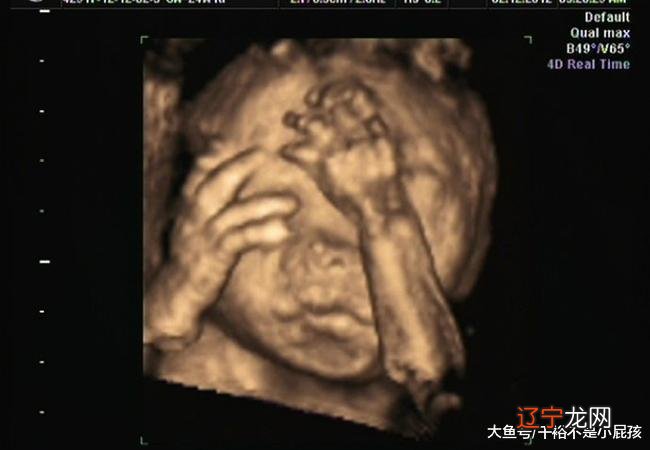

【【梦见生女孩】梦见生女孩是什么意思】其实生男生女的几率都一样,单纯依靠胎梦来判断肚子胎儿的性别是不科学的,另外如果孕妇出现梦多、做噩梦,白天精神不佳,并且因为梦境而产生心理负担,就对孕妇本人和胎儿产生不好的影响,而唯一有效的办法,就是放松身心,正确对待那些不必要的顾虑,消除那些不必要的精神负担,不必把胎梦看得那么神秘,有什么思想疑虑和心理负担应找医生咨询或治疗,使身心处于健康状态,愉快地度过孕期 。